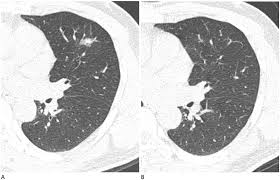

- 이전 영상과 비교하여 결절의 변화 여부 확인

- 결절 크기·형태·경계·석회화 여부 등 특징 분석

📆 폐결절 관리·추적 가이드라인

- 6mm 이하의 작은 결절은 정기적 CT 추적 관찰

- 6~8mm는 6~12개월 내 재촬영, 변화 없으면 18~24개월 후 재검

- 8mm 이상 또는 위험 소견 시 3개월 내 CT, PET-CT 또는 생검 고려